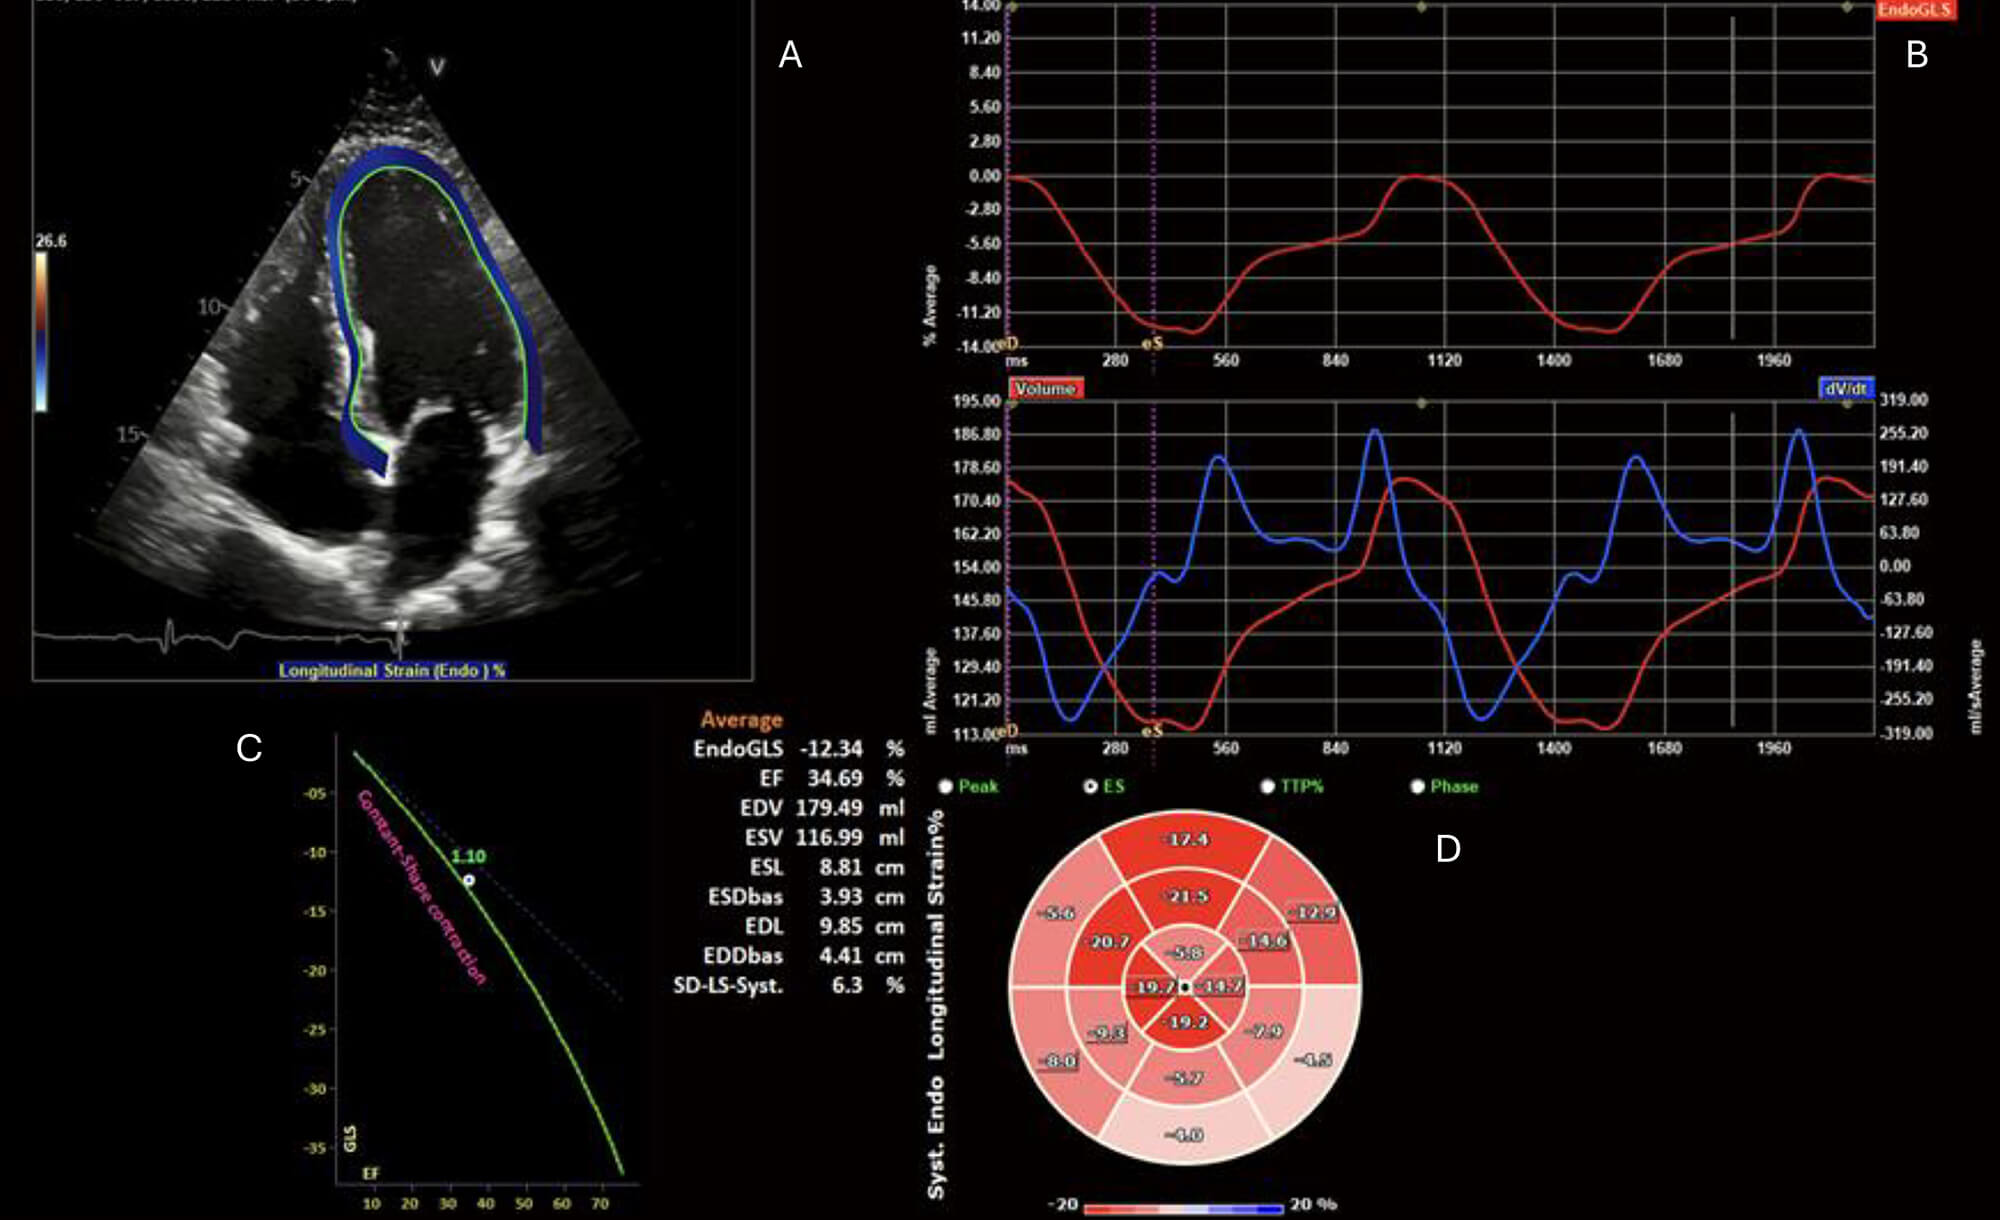

The advantages of parametric mapping lie in the ability to provide spatial visualisation and quantification of myocardial tissue changes seen in myocarditis. This allows for better assessment of diffuse disease processes and the study of the evolution of the disease process. T1 mapping measures the longitudinal relaxation time (T1), which is frequently elevated in myocarditis due to oedema, necrosis, or interstitial expansion associated with inflammation (Fig. 2A,B). Native, pre-contrast, T1 mapping is particularly useful for detecting diffuse myocardial oedema or fibrosis that may not be apparent with conventional imaging. It is therefore sensitive, but lacks specificity for the assessment of oedema. T2 mapping quantifies transverse relaxation time (T2), and elevated values serve as a more specific marker for myocardial oedema (Fig. 2C,D). Extracellular volume (ECV) is derived from pre- and post-contrast T1 mapping values and reflects extracellular matrix expansion and is elevated in areas of oedema or scar [30]. Utilising the combination of these three values allows for a comprehensive assessment of areas of myocardial scar and oedema, with the presence of elevated ECV, T1 and T2 being associated with adverse events in myocarditis, including arrhythmia and cardiac mortality [31].

Fig. 2.

Cardiac magnetic resonance parametric mapping. Cardiac magnetic

resonance imaging (MRI) T1 (A,B) and T2 (C,D) mapping of the myocardium in mid

short-axis (A,C) and four-chamber (B,D) views demonstrates focal increases in

relaxation times (T1 = 1281 ms; T2 = 63 ms) within the mid-lateral and

infero-lateral walls (arrows). Images acquired on Siemens Aera 1.5T scanner

(Siemens, London, England) (normal ref range T1